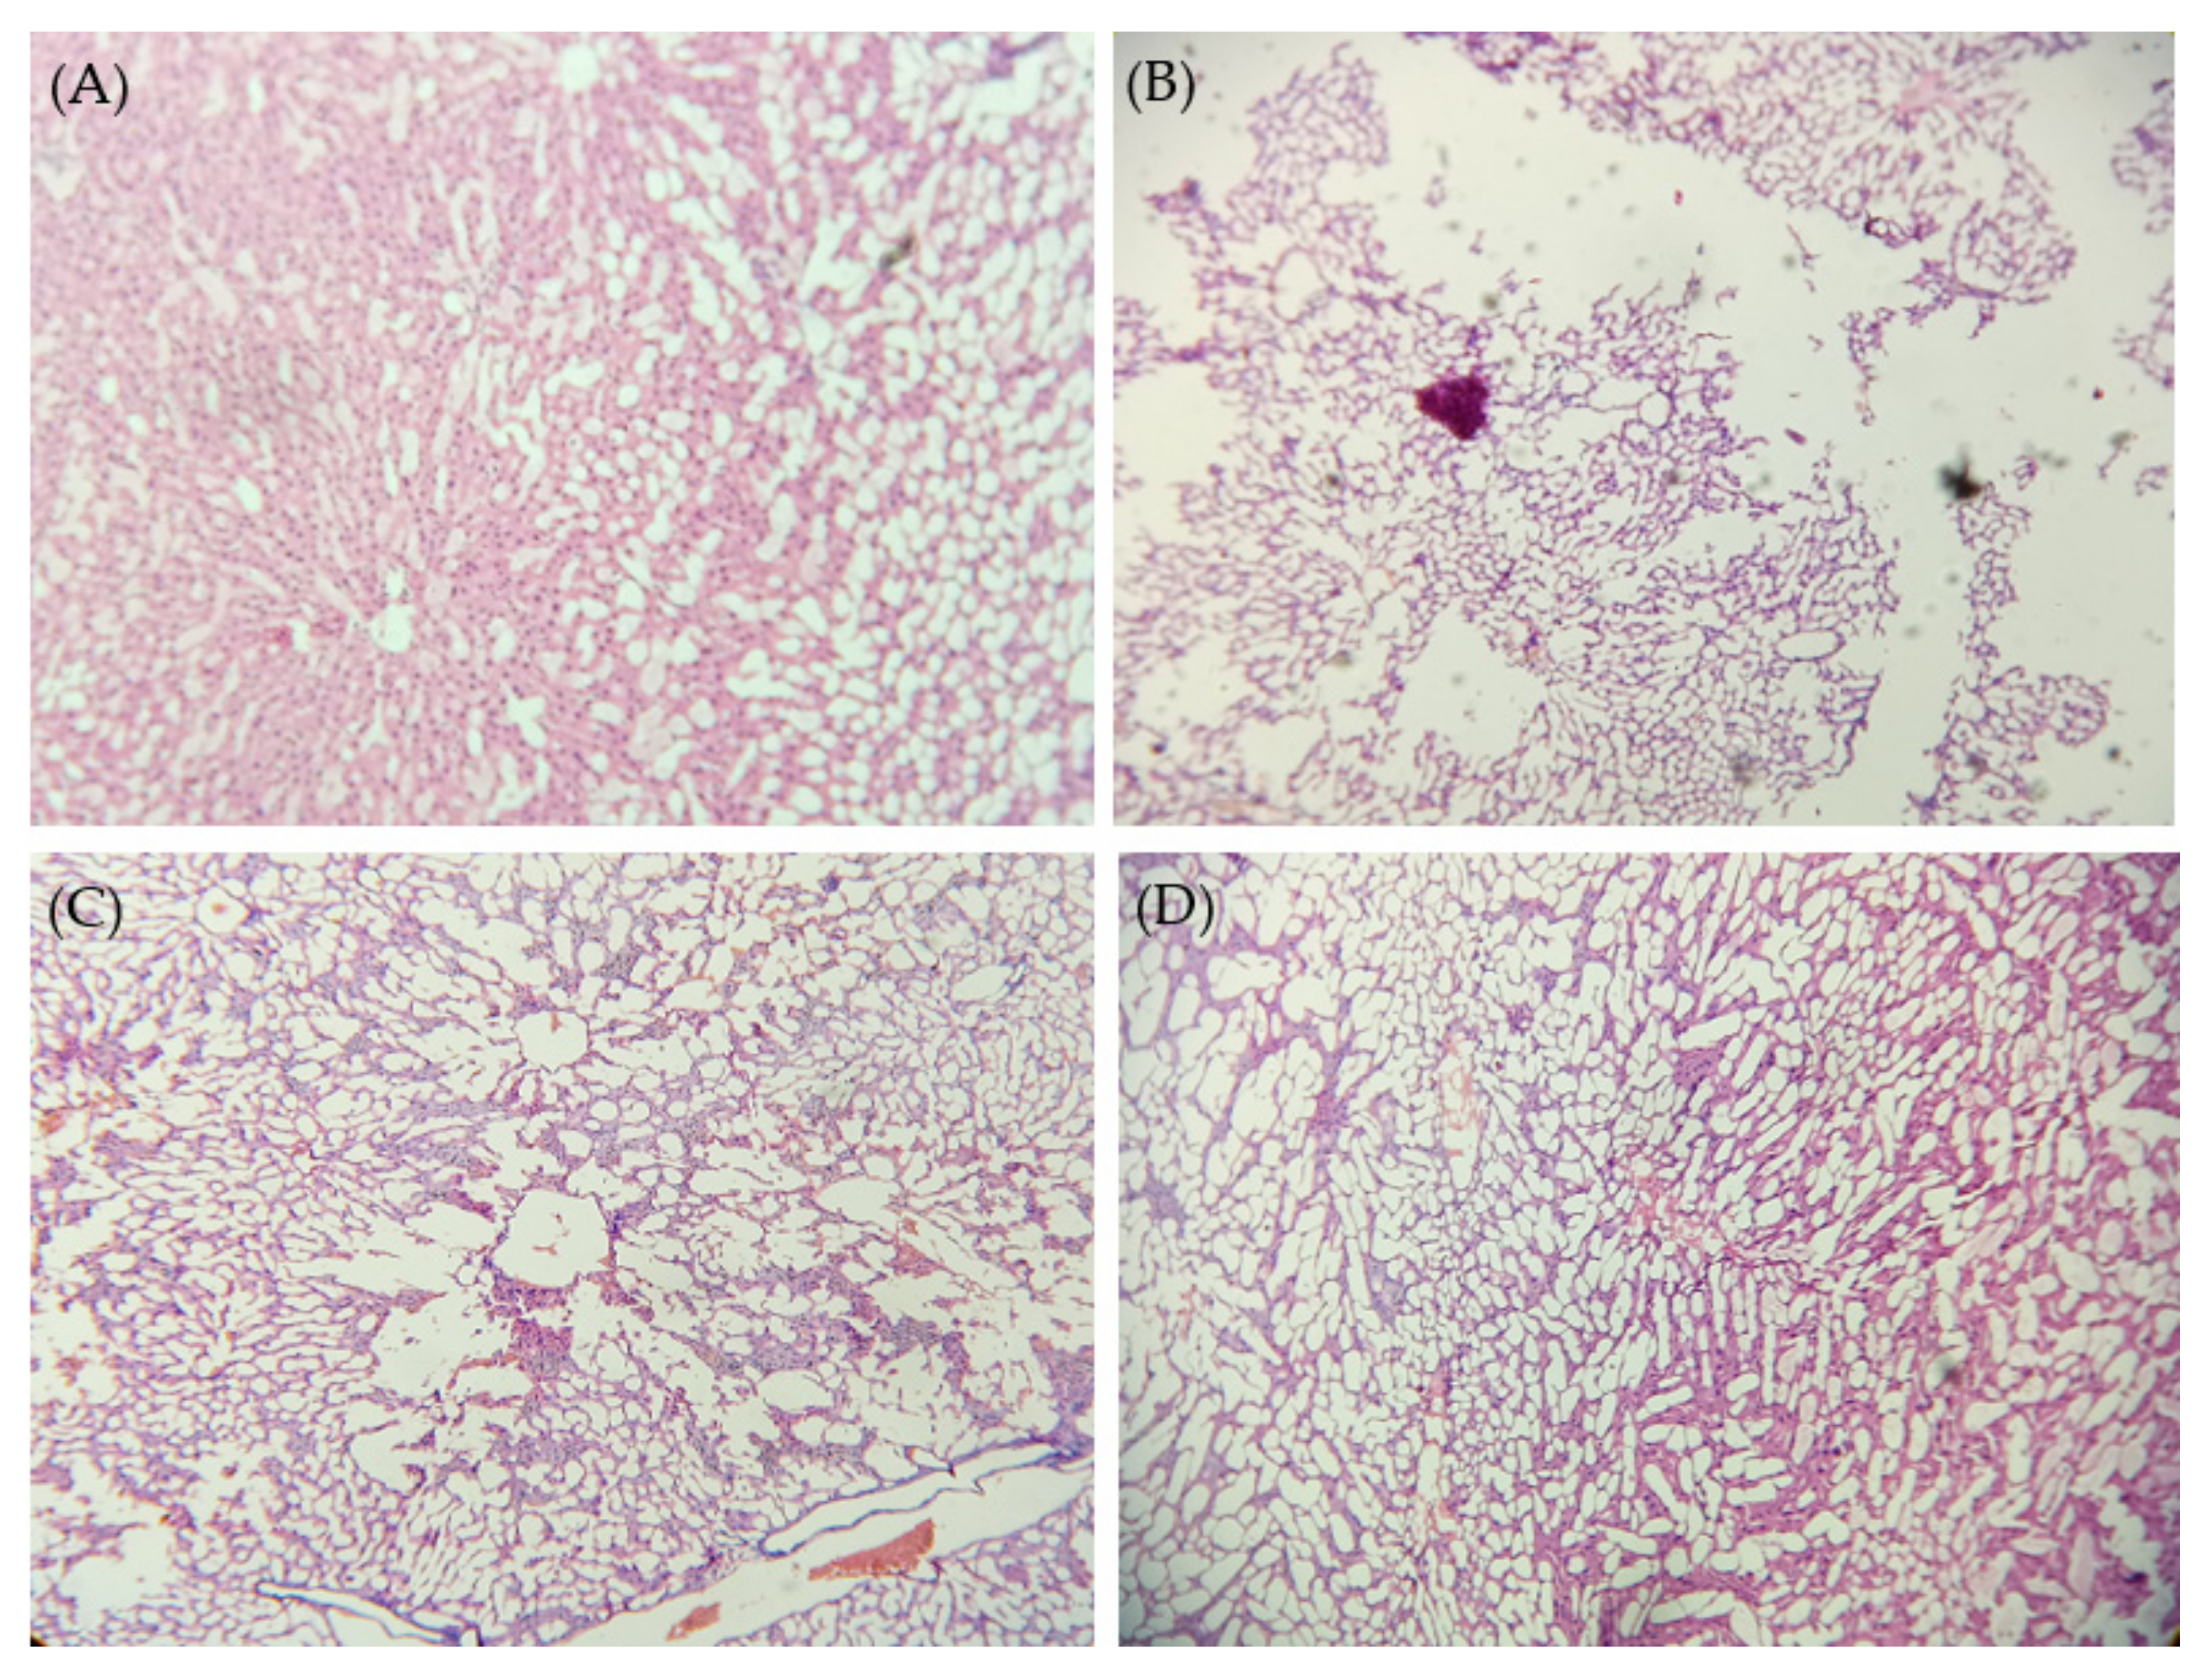

2.9. Histopathological Studies

3.7.3. Histopathological Studies